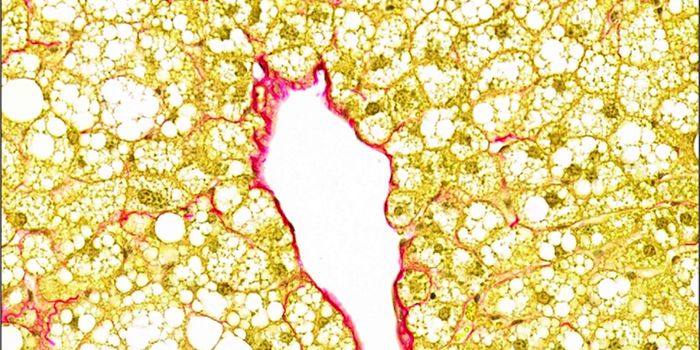

SEP 28, 2016ImmunologyA diet high in fat from specific sources is uniquely responsible for contributing to intestinal cancer through promoting ...

JUL 08, 2019Cell & Molecular BiologyNot all fat is the same. Researchers have examined how fat stored in different parts of the body can have different impa ...